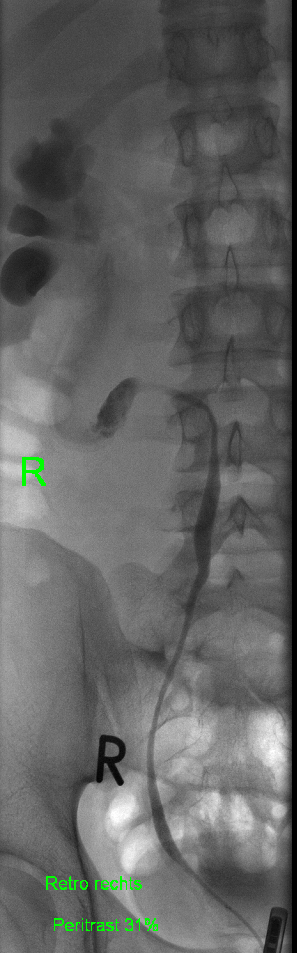

In diesem Fallbericht beschreiben wir einen 17-jährigen Patienten, der mit rez. ausgeprägten Koliken in unserer Abteilung vorstellig wurde. Initial erfolgte bei Hydronephrose °III und pos. Steinanamnese des Vaters eine CT-Abdomen nativ, welche bereits den V.a. einen retrocavalen Harnleiter rechts ergab. Eine Szintigraphie bestätigte eine urodynamisch relevante Obstruktion bei ausgeglichener Nierenfunktions. Bei Symptomatik erfolgte eine retrograde Ureteropyelographie mit JJ-Einlage. Im weiteren Verlauf wurde noch eine MRT-Angiographie durchgeführt, welche den Befund eindeutig bestätigte. Daraufhin erfolgte am 10.11.2025 die daVinci-assistierte Ureterureterostomie rechts in Linksseitenlage. Hierfür wurden 4 Arbeitstrokare und ein Kameratrokar verwendet. Die Gesamtoperationszeit lag bei 181 min, die reine Konsolenzeit bei ca. 100 min. Intraoperativ erfolgte ein JJ-Wechsel. Die Anastomose erfolgte mit einer 4.0 Quill-Naht in fortlaufender Technik. Der Blutverlust lag bei ca. 20 ml. Postoperativ waren die Schmerzen mit Novalgin gut beherrschbar. Die Entlassung erfolgte am 5. postoperativen Tag nach DK-Entfernung.